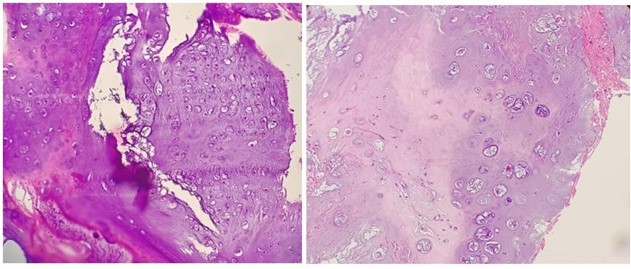

Histopathological examination showed chondroid tissue with a lobular pattern. There was a mild increase in cellularity with occasional binucleate nuclei and foci of mild nuclear atypia. Occasional mitosis and foci of myxoid change noted (Fig. 3).

These features were consistent with chondroid neoplasm, morphology favouring atypical cartilaginous tumour/chondrosarcoma grade I.

Figure 3: (A) Histopathology H&E stained slide (hematoxylin and eosin stain) at 200x magnification which demonstrates the chondroid matrix with lobular pattern. (B) H&E stained slide at 400x magnification showing increased cellularity, binucleate nuclei and nuclear atypia.